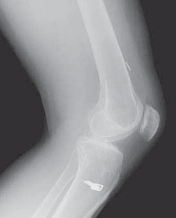

IMAGING AND OTHER DIAGNOSTIC STUDIES

3. Routine radiographs, including weight-bearing anteroposterior and lateral views as well as patellar views, should be performed. In the revision setting, these images allow for critical assesment of previous tunnel placement and assesment for possible bone loss at previous tunnels, which may require further evaluation and treatment.

1. Metallic fixation devices make previous tunnel placement easy to identify, but bioabsorbable screws and other types of fixation also can be evaluated for tunnel placement on these images (

FIG 1

).

2. These images also allow evaluation for possible evidence of osteoarthritis.

FIG 1 • A,B. Anterior cruciate ligament (ACL) reconstruction performed with an EndoButton (Smith & Nephew, Andover, MA) on the femur and staple fixation of the graft on the tibia. C,D. Anterior placement of the femoral tunnel in this primary ACL reconstruction performed with a two-incision technique. A B C

D

13. A common cause of failure related to surgical technique is anterior placement of a femoral tunnel, which often is detected on the lateral radiograph (

FIG 1D

).6,10 This may lead to tightening of the graft with knee flexion resulting in graft stretch-out or failure.